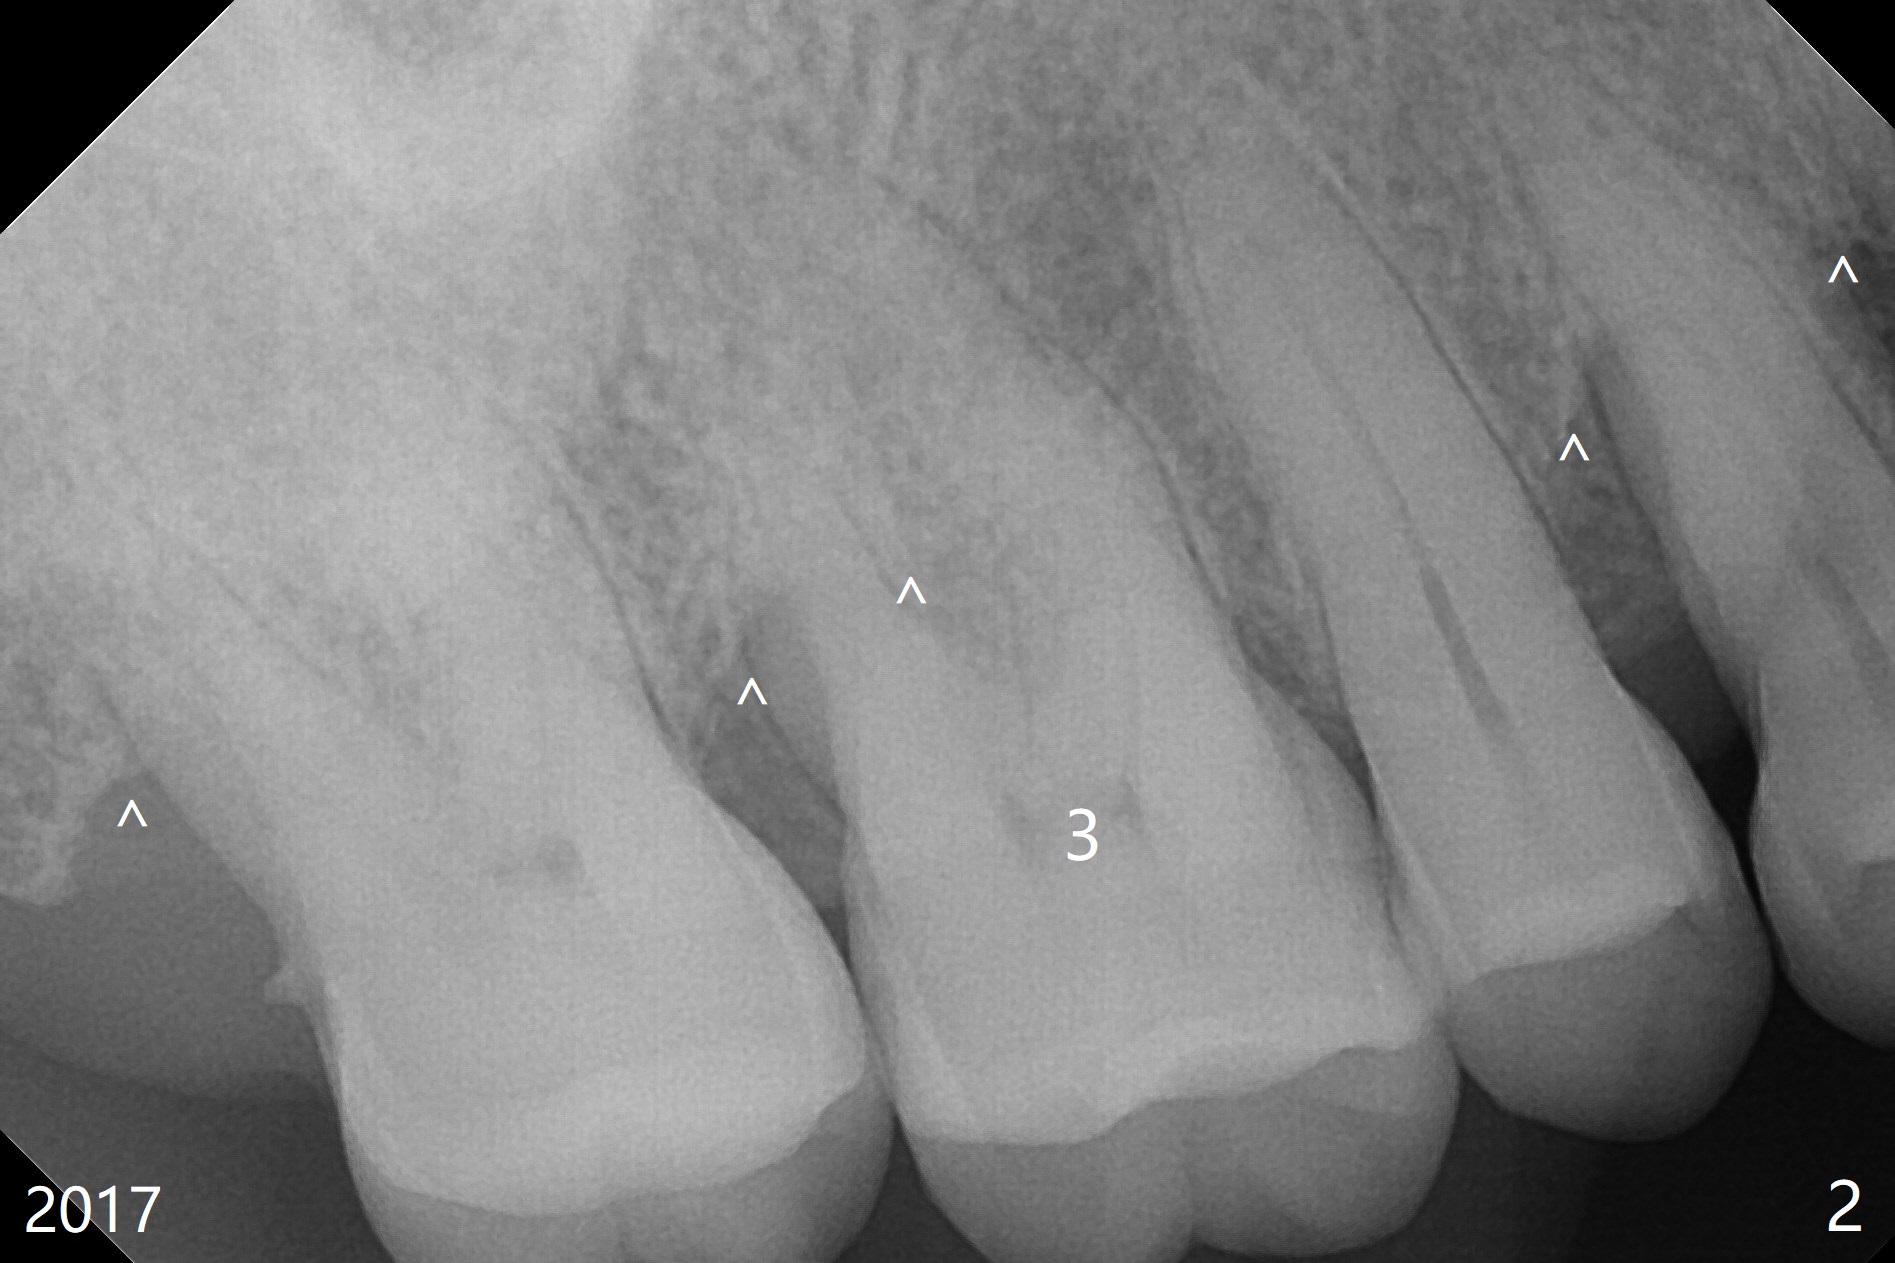

A 65-year-old woman has had signs & symptoms of crack tooth at #3 for the last 4 years (Fig.1-3). Finally the tooth is tender for mastication. Since the socket has infection and the bone is long (Fig.4 red line), an implant will be placed shy of the sinus floor (yellow dashed line). The bone loss (Fig.2,3 ^) may be associated with bruxism, which is detrimental to implant osteointegration. The immediate provisional should have enough occlusal clearance.